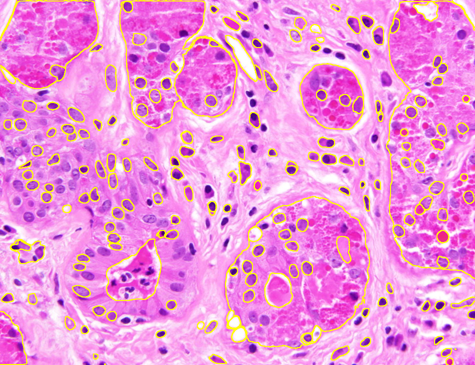

Dataset 1 comprises a synthetic video and two hematoxylin and eosin (H&E)-stained images collected from public online sources [71, 72]. H&E staining is standard in histopathology, with nuclei appearing blue–purple and cytoplasm pink. The images are provided in RGB format with varying image sizes and are used solely for qualitative illustration and timing comparisons, as no ground-truth annotations are available. The synthetic video consists of 74 MATLAB-generated frames. The first frame shows a 3D mitochondrial mesh generated via the isosurface function and rendered with Phong illumination, with the light source positioned above and to the right of the camera. Subsequent frames are obtained by rotating this initial view. This dataset was constructed to study segmentation under pronounced frame-to-frame illumination changes.

Representative samples from the three datasets are shown in Fig. 1. In (a), the first frame of the synthetic video in Dataset 1 illustrates the strong illumination gradients produced by distance-dependent shading together with orientation-dependent interactions between vertex normals and the light direction. The H&E images in (b) and (c), also from Dataset 1, depict a mast cell infiltrate from a patient with non-alcoholic steatohepatitis and cirrhosis and, respectively, a sample from a patient with sclerosing polycystic adenosis of the parotid gland; the former consists primarily of purple nuclei, white cytoplasm, and pink extracellular tissue. Subfigures (d) and (e) show two examples from Dataset 2 accompanied by their ground-truth nuclei annotations, while (f) and (g) present a representative image from Dataset 3 together with its corresponding cell mask.

Figure 1: Samples from Datasets 1–3. (a) First frame of the 74-frame video in Dataset 1 (1770 × 880) with a superimposed red mesh. (b,c) H&E-stained tissue images from Dataset 1 (1000 × 750; 950 × 730). (d,e) Cell images from Dataset 2 (600 × 600) with nuclei annotations. (f,g) Image from Dataset 3 (512 × 512) with annotation.